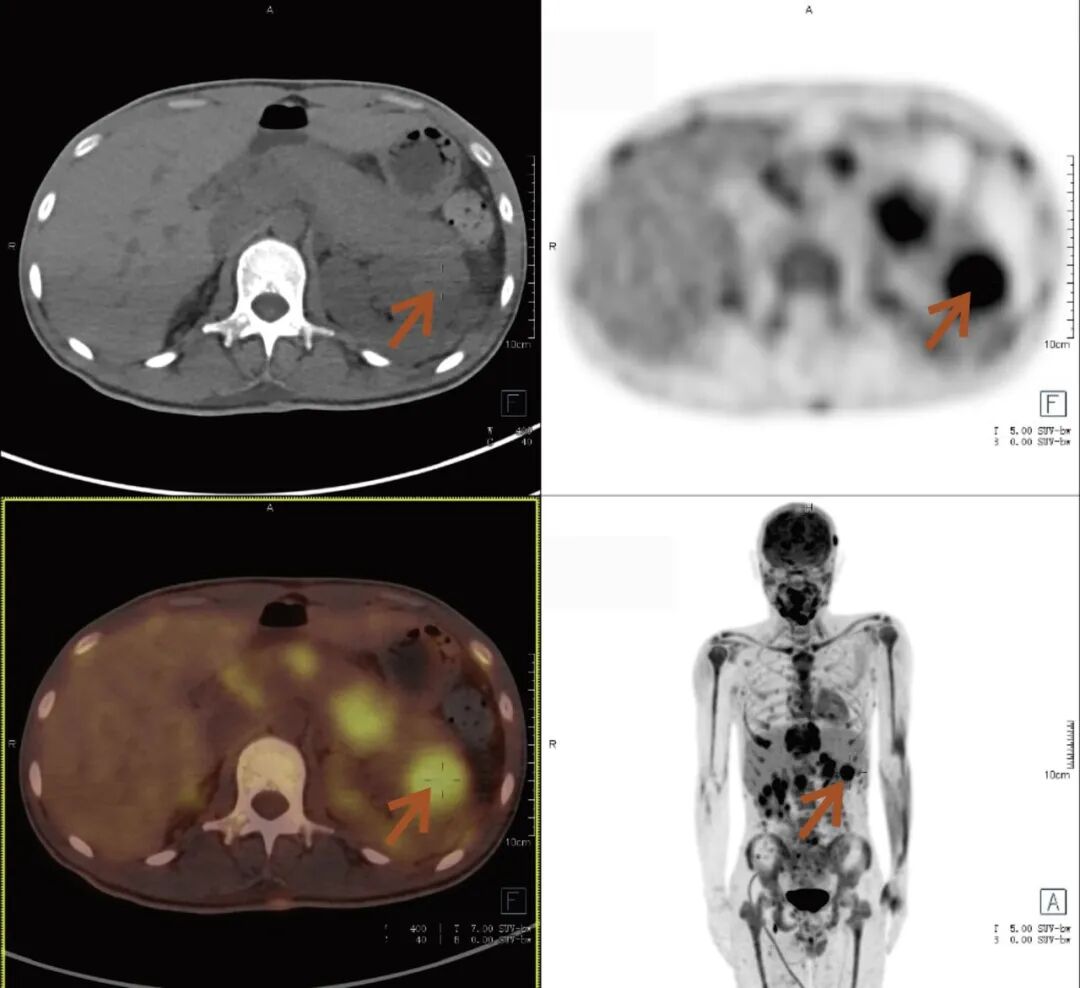

张先生(化名),因持续3个多月的腹痛、腰痛在外院就诊。初始CT检查发现其胸11椎体骨质破坏伴周围软组织肿胀,考虑为“脊柱结核”等感染性病变,并接受了中药治疗。然而,两个月后,张先生又出现了新的症状——牙痛。 经病理活检及免疫组化检查,最终确诊为极为罕见的Erdheim-Chester病。为全面评估这一可累及全身多系统疾病的侵犯范围、明确病灶活动性,并为制定精准治疗方案提供依据,张先生进行了全身PET/CT检查。 PET/CT检查图像: PET/CT检查结果: (1)中轴骨及四肢骨广泛FDG代谢活跃伴信号异常;其中胸10、胸11椎体病灶周围软组织增厚,累及邻近椎管内及双侧椎间孔、双侧胸膜,并与主动脉分界不清。 (2)全身皮下及肌层内多发结节及肿块,FDG代谢活跃;全身软组织广泛肿胀。 (3)鼻咽各壁增厚,顶后壁为著,FDG代谢活跃。 (4)甲状腺多发结节,FDG代谢活跃;双肾及胰腺多发结节及肿块,FDG代谢活跃;双侧阴囊内异常信号伴FDG代谢活跃; (5)左侧锁骨上窝、纵隔内(2L区、3A区)、降主动脉旁、左侧横膈前组、右侧腋窝、左肾周间隙、肠系膜区、双侧髂血管旁多发淋巴结,FDG代谢活跃; (6)心包局部呈结节状稍增厚,FDG代谢轻度活跃; 综上,结合临床,均考虑Erdheim-Chester病所致。 此次PET/CT不仅证实了已知的脊柱病变,更一次性揭示了临床尚未怀疑的、广泛存在于内脏、淋巴结及软组织的隐匿病灶,为疾病分期与治疗提供了决定性依据。